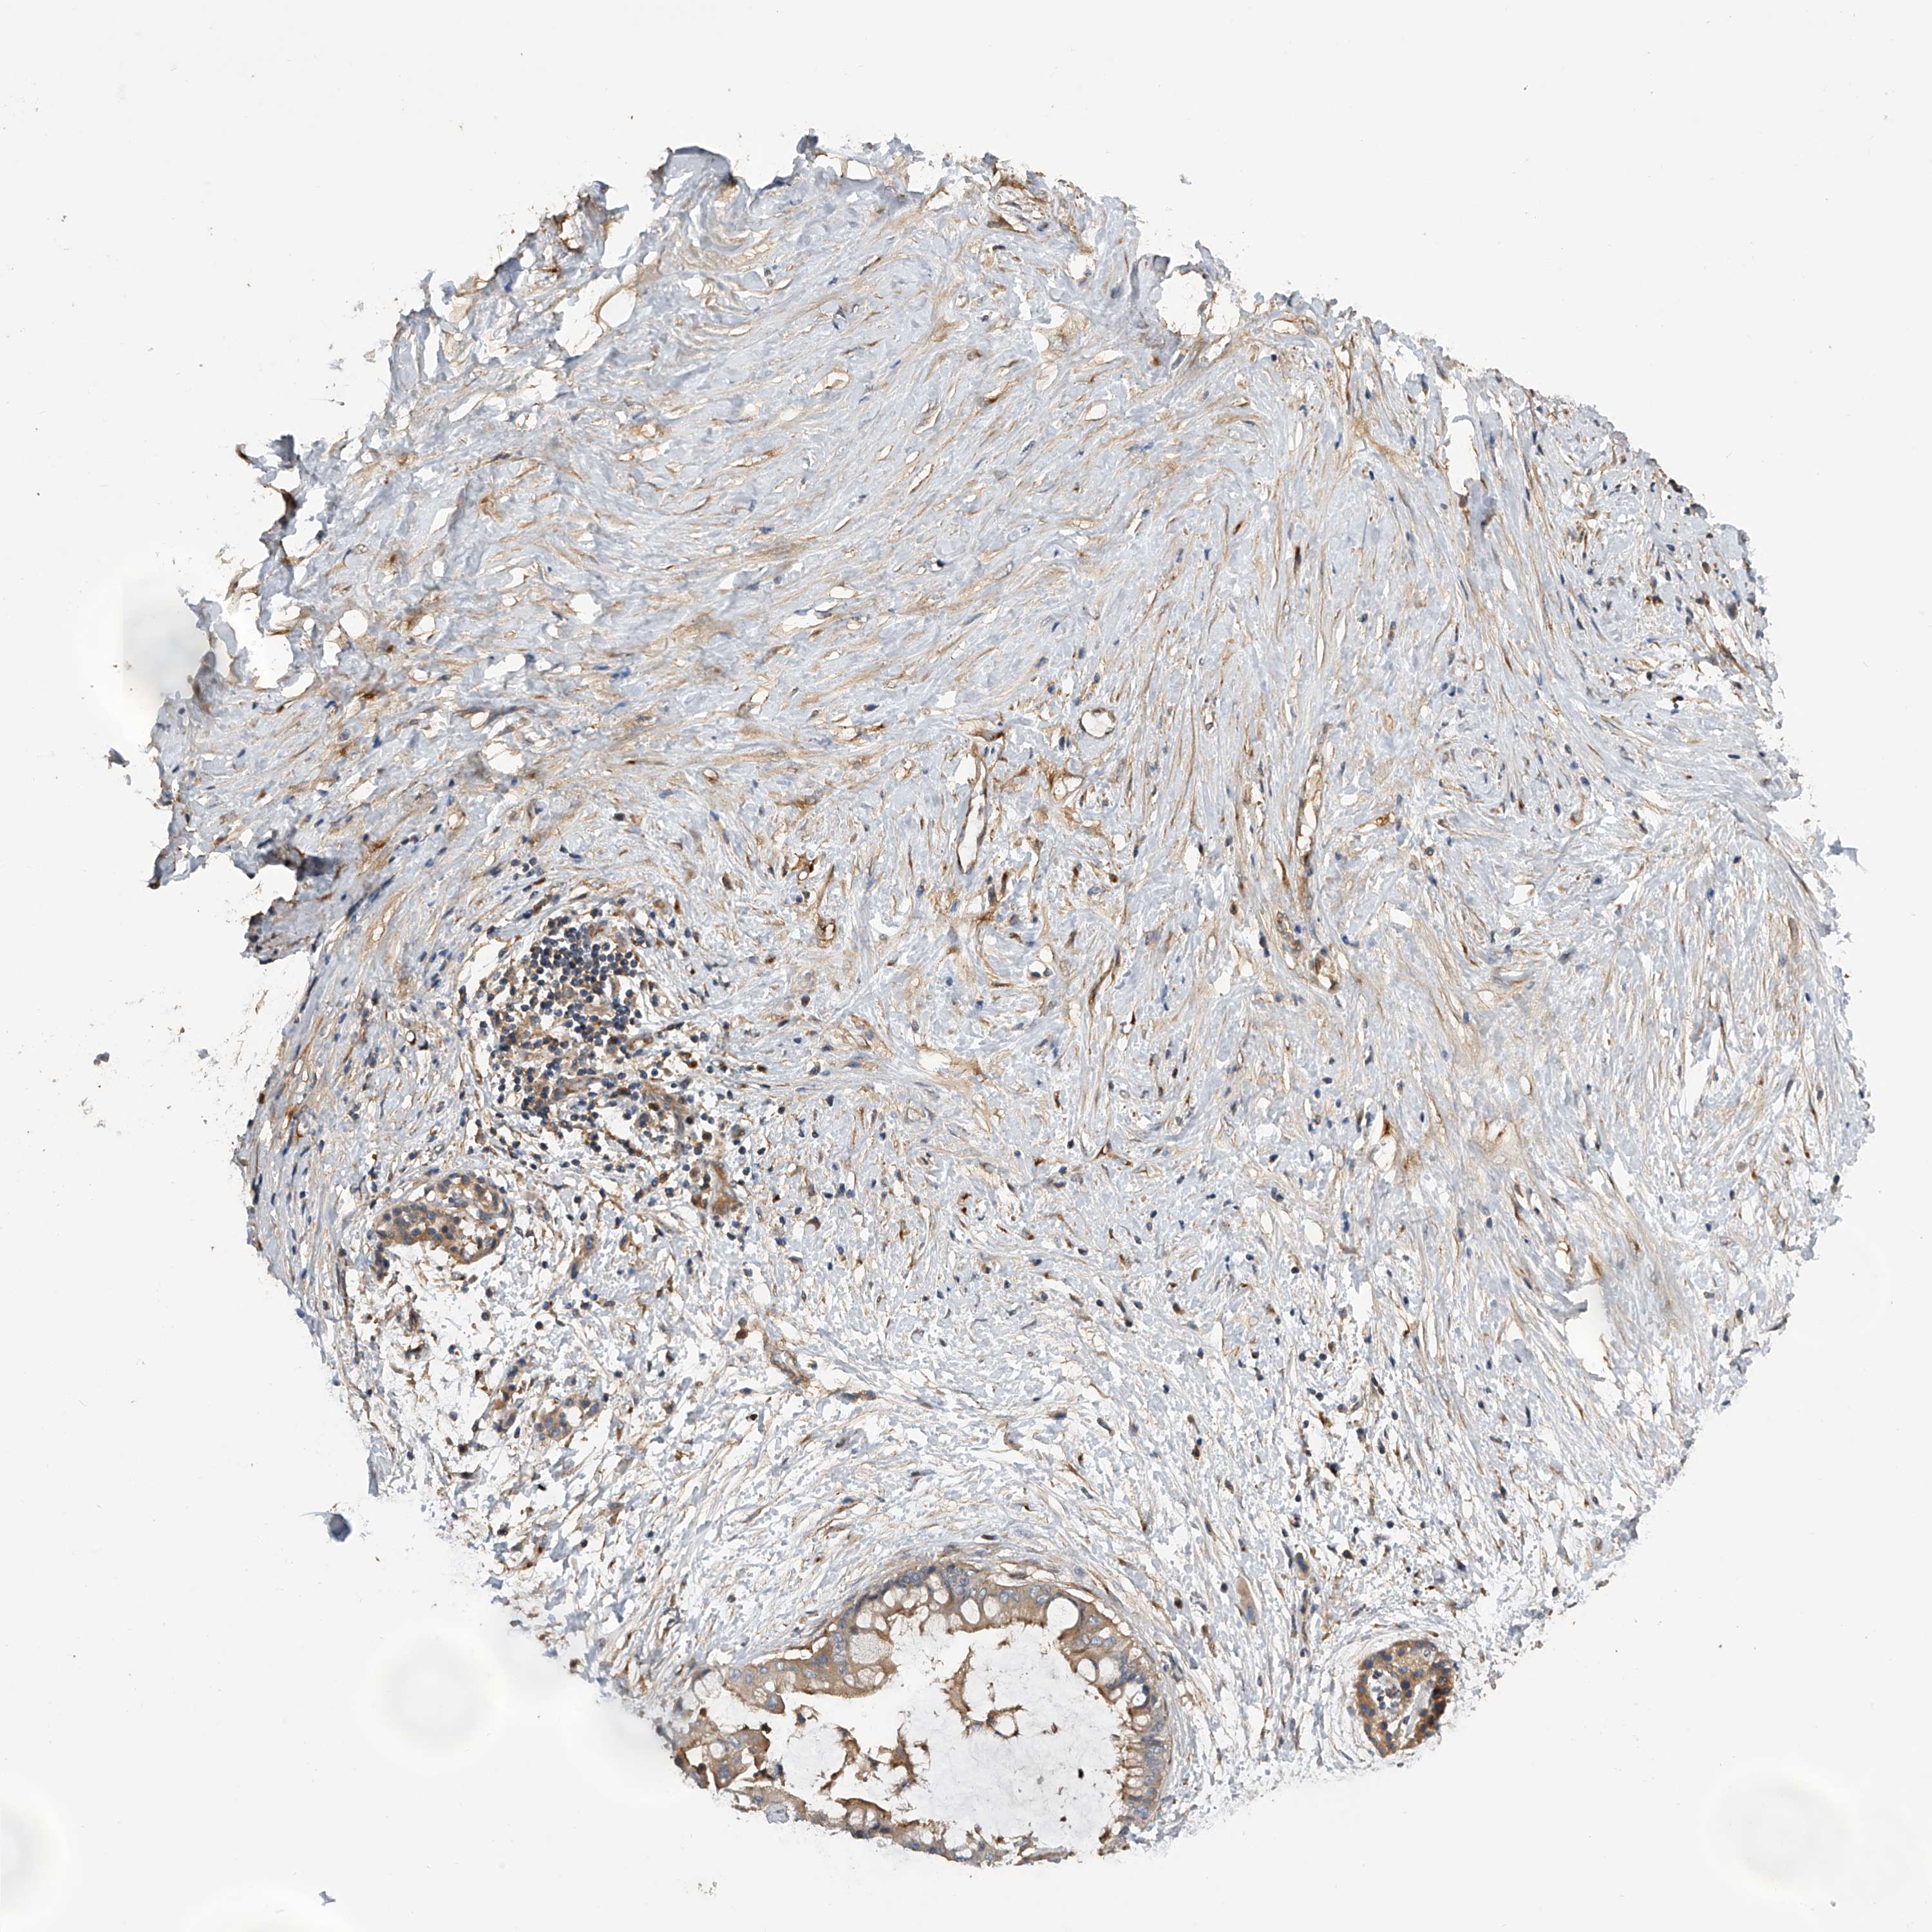

PANCREATIC CANCER - Protein expressioni

A mouse-over function shows sample information and annotation data. Click on an image to view it in a full screen mode. Samples can be filtered based on level of antibody staining by selecting one or several of the following categories: high, medium, low and not detected. The assay and annotation is described here.

Note that samples used for immunohistochemistry by the Human Protein Atlas do not correspond to samples in the TCGA dataset.

Antibody stainingi

Antibody staining in the annotated cell types in the current human tissue is reported as not detected, low, medium, or high, based on conventional immunohistochemistry profiling in selected tissues. This score is based on the combination of the staining intensity and fraction of stained cells.

Each image is clickable and will lead to virtual microscopy that enables deeper exploration of all samples and also displays staining intensity scores, fraction scores and subcellular localization as well as patient and tissue information for each sample.

Antibody HPA029412

Antibody CAB034366

Staining

High

Medium

Low

Not detected

Intensity

Strong

Moderate

Weak

Negative

Quantity

>75%

75%-25%

<25%

None

Location

Nuclear

Cytoplasmic/membranous

Cytoplasmic/membranous,nuclear

Adenocarcinoma, NOS